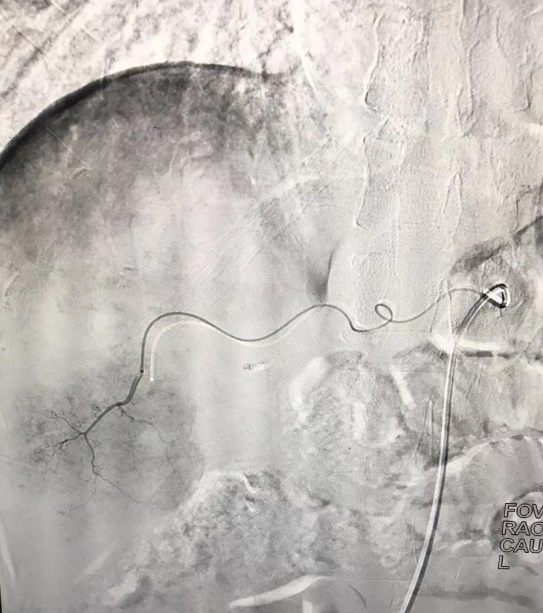

請介入科會診,進(jìn)行術(shù)前病例討論,排除介入禁忌,于5月20日下午15:30為該患者D-TACE+HAIC術(shù),術(shù)中造影發(fā)現(xiàn)患者肝動脈畸形扭曲,導(dǎo)絲反復(fù)進(jìn)入肝動脈受阻,最后在介入科醫(yī)師的不懈努力下,最終使用微導(dǎo)管超選至腫瘤供血動脈,以載藥微球+鹽酸表柔比星60mg栓塞腫瘤供血動脈,載藥微球持續(xù)釋放化學(xué)藥物,手術(shù)順利完成。

術(shù)前造影顯示腫瘤由肝動脈分支供血,血管增粗屈曲,腫瘤染色顯影明顯。